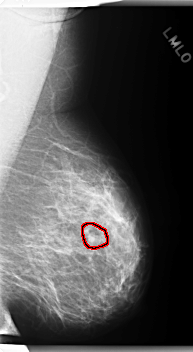

C_0277_1.RIGHT_MLO

LEFT_MLO LINES 5976 PIXELS_PER_LINE 3272 BITS_PER_PIXEL 12 RESOLUTION 50 OVERLAY

FILE: C_0277_1.LEFT_MLO.OVERLAY

TOTAL_ABNORMALITIES 1

ABNORMALITY 1

LESION_TYPE MASS SHAPE LOBULATED MARGINS CIRCUMSCRIBED

ASSESSMENT 3

SUBTLETY 4

PATHOLOGY BENIGN

TOTAL_OUTLINES 1

BOUNDARY